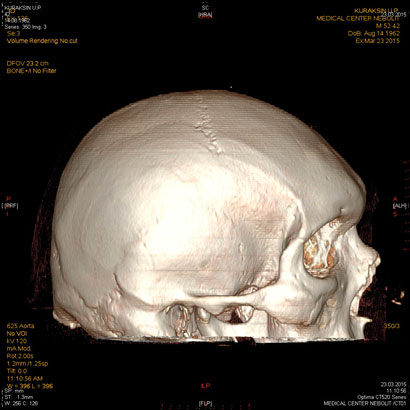

МСКТ головного мозга.

С появлением КТ значение обычной рентгенографии в выявлении переломов черепа значительно уменьшилось, назрел вопрос о пересмотре диагностической тактики при ЧМТ. В настоящее время следует считать правилом, что при наличии соответствующей аппаратуры в первую очередь необходимо проведение компьютерной томографии.

МСКТ является прекрасным методом выявления травматических повреждений, гематом, переломов, ретробульбарного скопления воздуха. КТ и МРТ обладают одинаковой чувствительностью в выявлении орбитальных опухолей: глиома, менингиома, лимфангиома, гемангиома, гемангиопероцитома и др, а также внеконусных образований: опухоли слезной железы, дермоид, лимфома, псевдоопухоли, метастазы, тиреоидная миопатия.

КТ и МРТ обеспечивают хорошую визуализацию турецкого седла. Однако МРТ обладает рядом преимуществ-более хорошее мягкотканое разрешение, недостаток-плохо видит кальцинаты. В свою очередь МСКТ является методом выбора при всех неотложных состояниях с травмами головы.

МСКТ остается методом выбора и особенна эффективна при обызвествлениях, инородных тел, костных структур. Некоторые опухоли нр гемангиома лучше видны при МРТ. При бактериальных поражениях мозга-абсцессах, менингитах,эмпиемах могут возникать трудности диагностики с опухолевым поражением, что требует введения контраста.

Клинические показания:

- травма головного мозга, лицевого черепа с подозрением на внутричерепное или субарахноидальное, субдуральное кровоизлияние, посттравматические последствия

- дифференциальная диагностика геморрагического и ишемического инсульта

- диагностика венозного тромбоза, внутримозговых гематом, САК

- подозрение на опухоль и вторичное поражение

- подозрение на воспалительный процесс (абсцесс)

- головная боль быстро прогрессирующая или длительная до 2 мес, не объясняемая другими причинами

- изменения в костях свода и основания черепа

- диагностика селлярных опухолей при невозможности проведения МРТ

Подготовка: не требуется

Предварительное рекомендуемое обследование: заключение невролога МСКТ головного мозга с вв усилением необходима при подозрении на опухолевый процесс, инфекционное поражение.